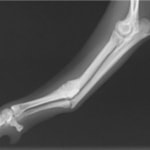

ペルシャ猫 11ヶ月齢 雄

他院にて左大腿骨遠位の成長板骨折(salter-harrisⅠ型)が認められており、治療相談を目的として来院。当院にて、キルシュナーワイヤーを用いたピンニングにより骨折部位の整復を行いました。術後の経過は良好で、現在も経過観察中です。

術前レントゲン